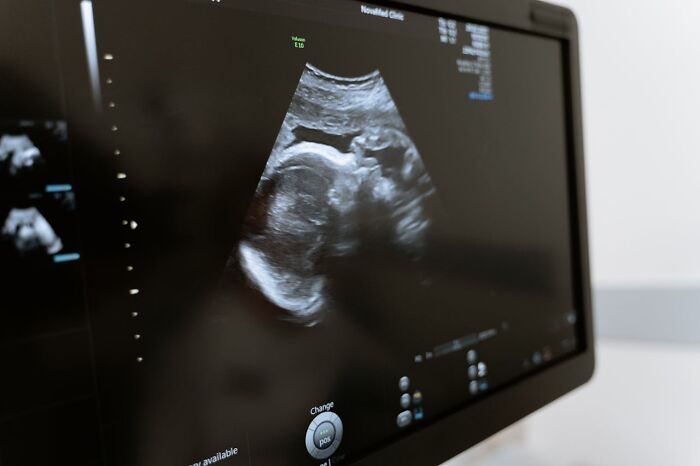

When I was an ultrasound student, a woman came in for her 20wk anatomy scan. It was right before Christmas. All her family was in town, and she was going to have a gender reveal. Her baby had anencephaly (absent brain), acrania (absent skull bones), omphalocele (herniation of the intestines into the cord), and a club foot. The Ob doc asked her if she wanted to be induced right then and there or wait until after the holidays. She chose to terminate her pregnancy immediately. I can’t even imagine how she was feeling. The baby looked like an alien.

Her heartbeat concealed mine, so a month before my brother's due date the doctor finally realized that there were two of us. This was in 1985 ultrasounds weren't nearly as good as they are now.